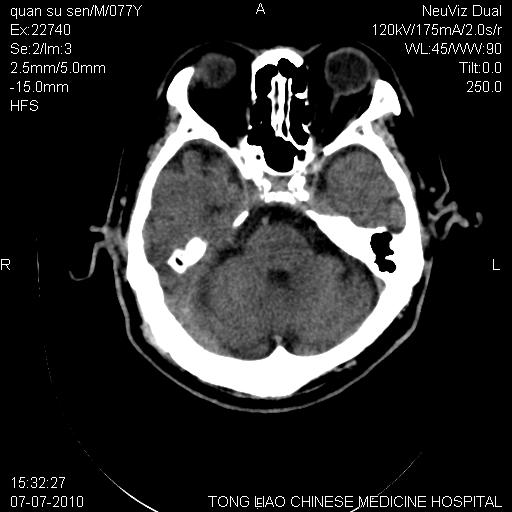

标题: CT27542:小脑病灶

平时经常遇到这样的病例,请问大家,是小脑萎缩还是小脑梗塞?

第一例,头晕、呕吐,复视,左侧肢体麻木

都是单侧小脑半球出现片状低密度灶,可以诊断脑萎缩吗?还是小脑梗塞?

桥---小脑角池 小脑沟增宽 萎缩

ct上显示小脑上沟,就提示小脑萎缩

不是小脑前下动脉梗塞的形态 所以是萎缩

小脑萎缩 ,所致蛛网膜下腔增宽。